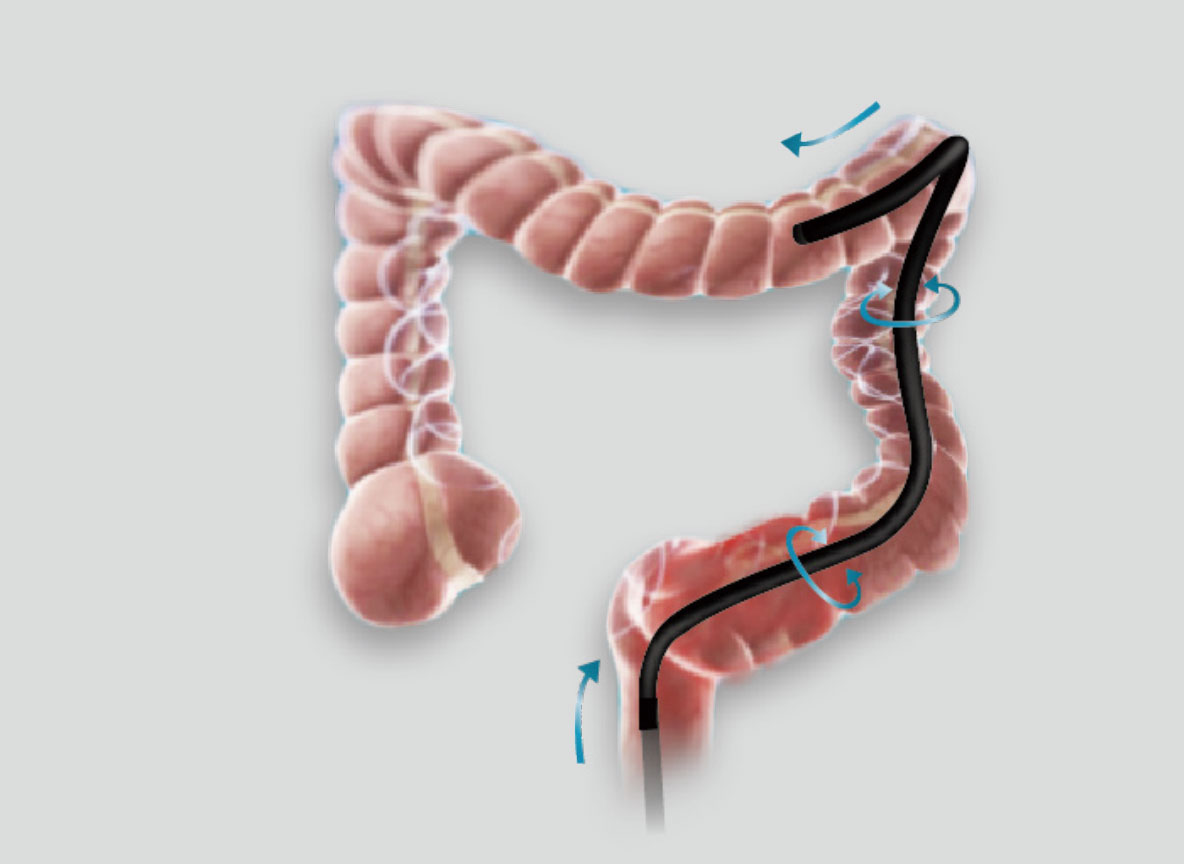

弯曲角度大,方便观察食管下段贲门、胃底部等难以观察到的部位,减少盲区。

带来镜体插入及诊疗新体验。

在临床操作中,时刻保持黏膜清洁和视野清晰,更快寻找出血点,满足临床治疗。